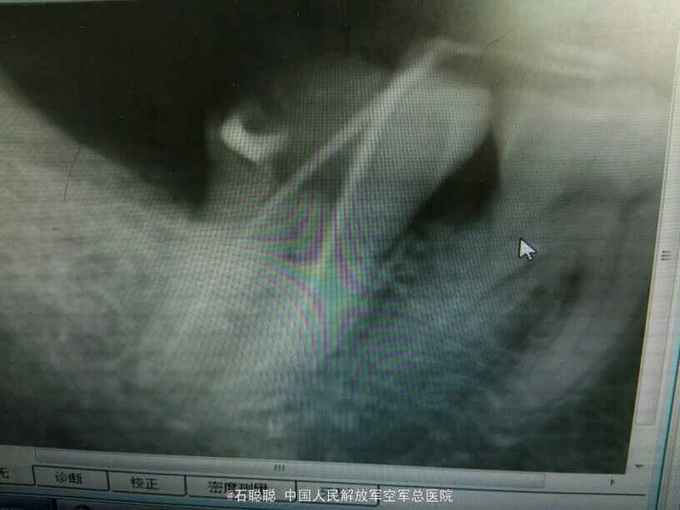

检查:右下7远中合面银汞充填体,边缘发黑,探针可探入,探痛+,冷+,叩痛-,不松动,牙龈未见异常 根尖片:右下7远中冠方见高密度充填影像,下方密度减低,近髓

诊断:右下7牙髓炎 治疗计划:右下7RCT后冠修复 处置:右下7“利多卡因”局麻下开髓,揭顶,探及近颊、近舌、远中3和根管口,略疏通,见血性渗出,冲洗,干燥,置失活剂,氧化锌暂封 一周后复诊:去除右下7暂封,测工作长度,近舌=19mm,扩大至30#,近颊=远中=18mm,扩大至35#,冲洗,干燥根管及髓腔,置CP棉球,氧化锌暂封 一周后复诊: 查:右下7叩痛-,不松动,氧化锌完整在位 处:去除右下7氧化锌暂封,试主尖,冷侧压充填,氧化锌暂封,建议一周后修复